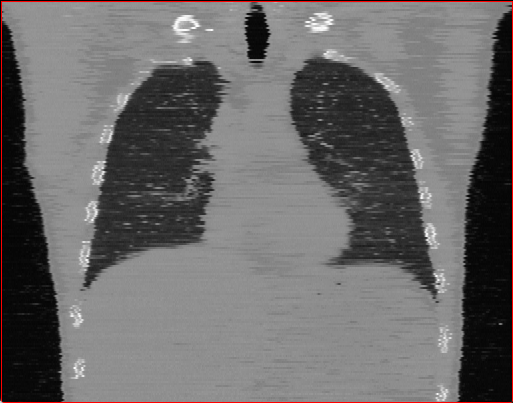

Figure 2: Qualitative comparison across axial (top row), sagittal (middle row), and coronal (bottom row) views. Columns correspond to different methods. MAISI-DDPM and MAISI-v2 in this figure are unconditional synthesis which do not use ControlNet or segmentation maps.

Qualitative Evaluation:

Figure 2 presents representative slices from the axial, sagittal, and coronal planes. GenerateCT (Hamamci et al. 2024) is a 2D model, so it lacks inter-slice consistency, leading to poor image quality in the sagittal and coronal views. MedSyn (Xu et al. 2024) produces noticeably blurry results with mosaic-like artifacts, such as region inside the red box. HA-GAN (Sun et al. 2022) generates visually sharp images but with mosaic-like artifacts, such as region inside the red box. Also, its voxel spacing is not available, which limits its applicability in real-world medical imaging tasks. Moreover, all three methods are restricted to synthesizing small anatomical regions. In contrast, both MAISI and MAISI-v2 are capable of generating high-quality 3D volumes that span larger body regions while preserving fine anatomical details and realistic structure.